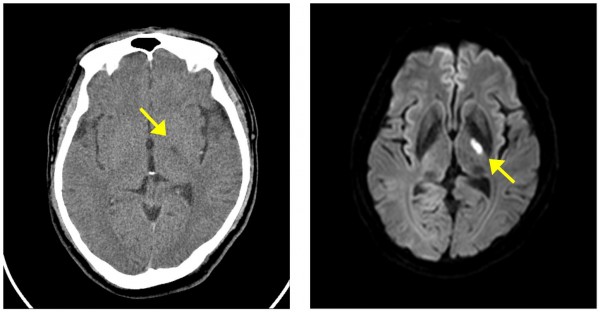

죄측 기저부로 가는 혈관이 막혀 우측 팔에 힘이 빠진 58세 환자의 영상